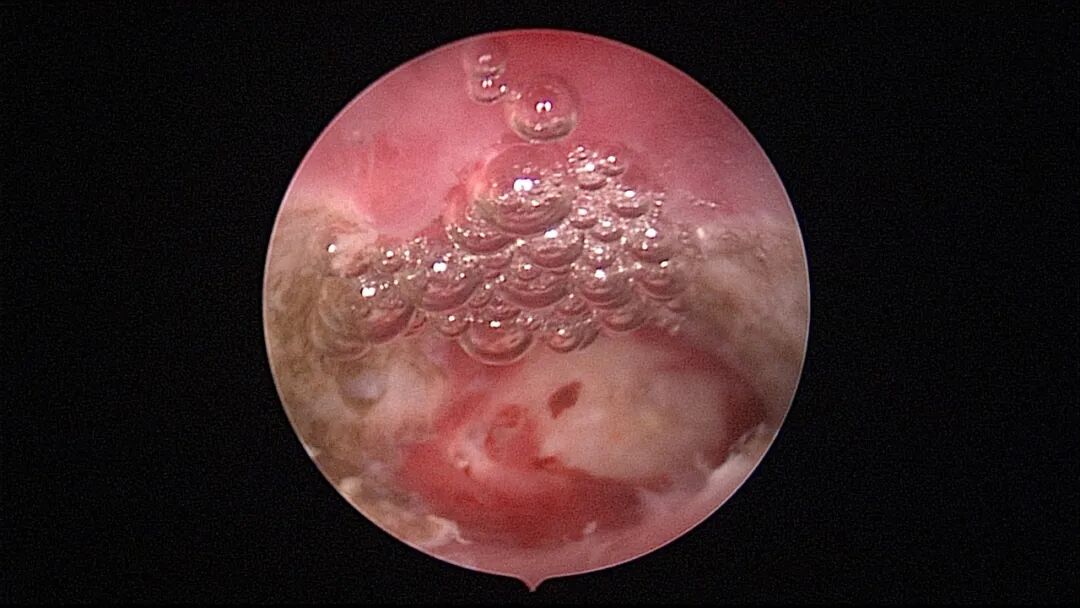

第八次宫腔镜:2025年7月宫腔镜二探取球囊,宫腔形态正常,双侧输卵管开口可见,内膜薄,片状充血。球囊在宫腔具有持续塑形作用,分粘术中没有显露的右侧输卵管开口已自我修复。